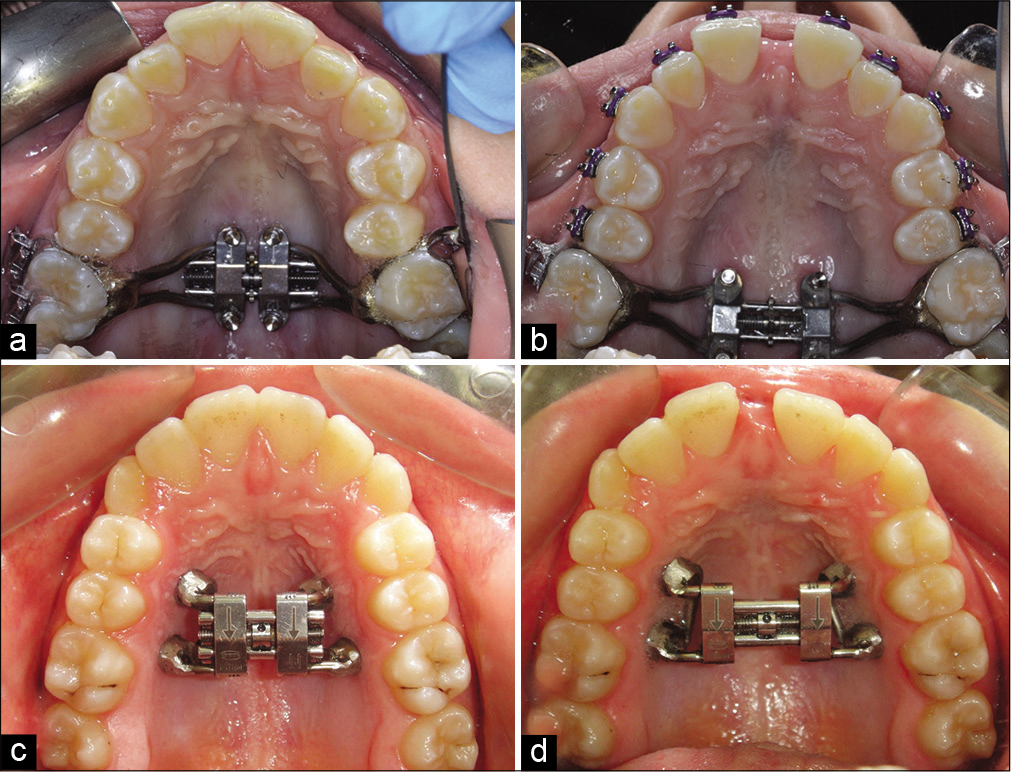

RPE (Rapid Palatal Expander) or RME (Rapid Maxillary Expander) is the least invasive expansion technique which uses tooth-borne expanders to widen the upper jaw. The device is placed in the roof of the mouth and anchored to the teeth, resulting in forces applied directly to the teeth. The expansion is achieved by turning the screw (the most popular type is the Hyrax screw), which is generally placed in the middle of the appliance. The forces will result in opening of the palatal suture and new bone being formed in the palate. While this is effective for skeletal changes in patients at a young age which can opt for a rapid (one turn of the screw per day) or slow expansion (at a more physiological rate of 1 turn every other day), it can lead to more dental than skeletal changes for older patients, with possible excessive tipping of the teeth and other complications.

MARPE (Mini-screw or Mini-implant Assisted Rapid Palatal Expansion), also known as MSE (Maxillary Skeletal Expansion) is an appliance positioned and anchored directly on the maxillary bone, bringing horizontal expansion forces close to the midpalatal suture. There are different variations of the appliance, some with connecting arms attached to the teeth, others without teeth anchorage. When the teeth anchorage is present, the appliance is referred to as hybrid or tooth-bone-borne appliance. Studies have shown that arms prevent the distal rotation of the teeth when the appliance is activated.